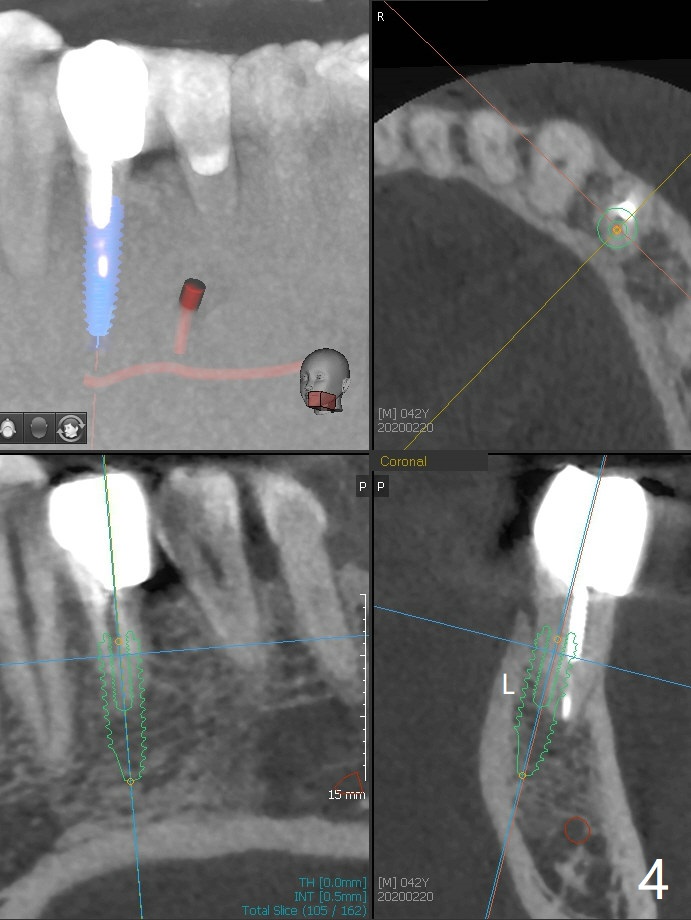

A 42-year-old man has been our patient for 3-4 years (Fig.1). An asymptomatic fistula develops lingual to the tooth #21 (Fig.2). An oblique fracture line appears to be next to a post (Fig.3 ^). A 3.5x11.5 mm implant seems to be able to be placed immediately lingual to the thick lingual plate with guide (Fig.4 L). No buccal deviation will occur with sufficient buccal gap. Design of an immediate implant at #21 (coronal section, Fig.5). In fact the root remains in place first (i.e., extract the crown first, Fig.5'). When osteotomy is done with the last drill 4x11.5 mm, there will be no deviation because of even counteraction between the buccal root and the lingual plate (Fig.6'). Then the root will be removed. But the 4.5x11.5 mm implant may be deviated buccal because of implant engagement into the lingual plate without buccal counteraction. Therefore, a 4x13 mm implant will be placed following 3.5x13 mm (last) drill. The implant is placed between the mesial and distal walls (Fig.7 sagittal section).